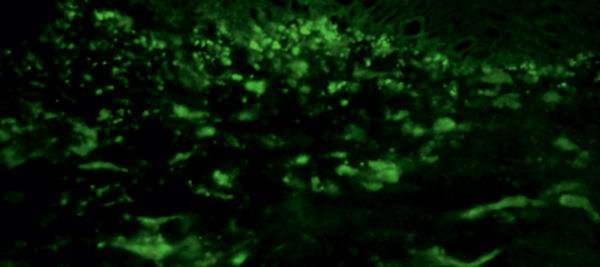

Direkte Immunfluoreszenz einer periläsionalen Hautbiopsie zeigt granuläre IgA-Ablagerungen an der dermoepidermalen Junktionszone (x 250).